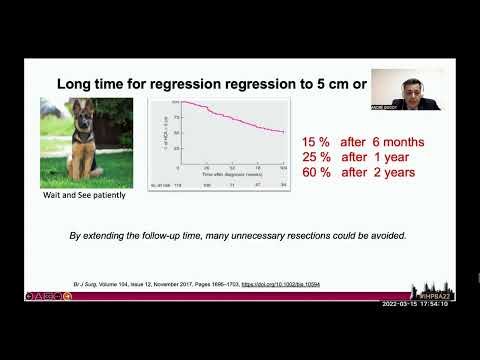

DEB17: Hepatic Adenoma: Time for Expanding the Conservative Management? Yes/No

Debate 17: Hepatic Adenoma: Time for Expanding the Conservative Management? Yes/No